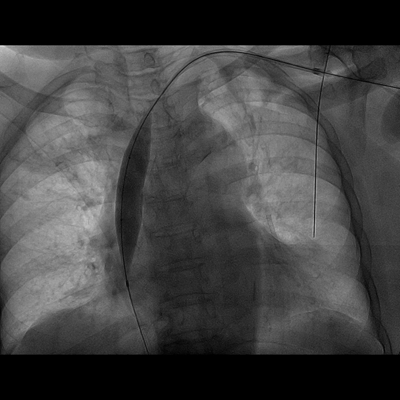

72岁钟阿姨,患尿毒症3年多,长期在我院维持性血液透析治疗,有糖尿病基础疾病,血管条件差,无法行动静脉内瘘手术建立血管通路。钟阿姨曾于2012年底在我院植入右侧颈内静脉半永久透析管,1年后因管路血流不通畅,予以行左侧颈内静脉半永久透析导管术,继续规律血液透析,近期因管路血流量不佳入我院住院治疗。入院后查CTV提示左侧颈内静脉纤细,上腔静脉怀疑血栓,右侧颈内静脉狭窄。由于考虑手术风险高,手术难度较大,肾内科严跃红主任医师邀请广州市第一人民医院放射介入科陈国东副主任医师,联合我院心血管介入科邓天明副主任医师和DSA室医护人员,术前全面评估,术中精细操作,血管造影显示:左侧锁骨下静脉、头臂静脉、上腔静脉上中段狭窄,上腔静脉下段完全闭塞,遂用三个球囊对狭窄闭塞的静脉血管进行逐级扩张成形后,上腔静脉血管复通,DSA引导下辅助半永久透析导管植入,手术成功。

球囊扩张